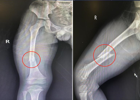

近日,阳西总医院人民医院骨一科成功为一名5岁的股骨骨折男孩小江实施了闭合复位、弹性髓内钉内固定微创手术。术后复查骨折断端对位对线良好,畸形得到有效纠正,效果良好。 一周前,小江因车祸受伤倒地,受伤后右大腿疼痛、肿胀、畸形、活动障碍,X线检查,提示为右股骨中上段骨折。 患儿骨折移位明显,如果采用手法...2023-02-23